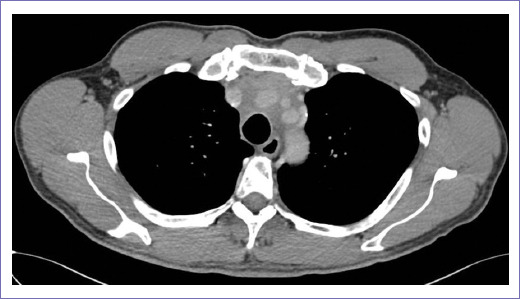

En diciembre de 2021 acudió a un mes del término de tratamiento con radioterapia, refiriéndose asintomático. Con signos vitales en parámetros de normalidad. Presentando radiodermitis G1 por CTCAE v5.0. En febrero de 2022 se realizó TC de tórax que reportó en mediastino anterior una lesión tumoral con densidad de tejidos blandos y calcificaciones gruesas que envuelve el tronco braquiocefálico derecho, carótida común izquierda y subclavia ipsilateral con calcificaciones gruesas localizadas en el espacio prevascular de menor tamaño y densidad, con reducción de 0.4 cm en su diámetro axial, comparado con estudio previo (Fig. 4).

Figura 4 Tomografía computarizada simple y contrastada de tórax de febrero 2022 de valoración de respuesta a tratamiento. Corte axial donde se observa tumoración con densidad de tejidos blandos que envuelve el tronco braquiocefálico derecho, sin ocluirlo, con reducción de 4 mm en diámetro axial.

En cuanto a las características por imagen, las imágenes de cortes transversales mediante TC, resonancia magnética y ultrasonografía permiten la identificación de diferentes elementos dentro de estos tumores, incluidos los tejidos blandos, los líquidos, la grasa y el calcio. En este paciente, mediante TC, se documentó un tumor mediastinal en el compartimento anterior, con densidad de tejidos blandos, en los cuales se apreció mayor involución tumoral tras el tratamiento con radioterapia, así como calcificaciones gruesas envolviendo al tronco braquiocefálico derecho, carótida común izquierda y subclavia ipsilateral con calcificaciones gruesas localizadas en el espacio prevascular, características propias de los teratomas maduros reportadas ampliamente en la literatura, a excepción del componente quístico, que en nuestro paciente no se documentó13.